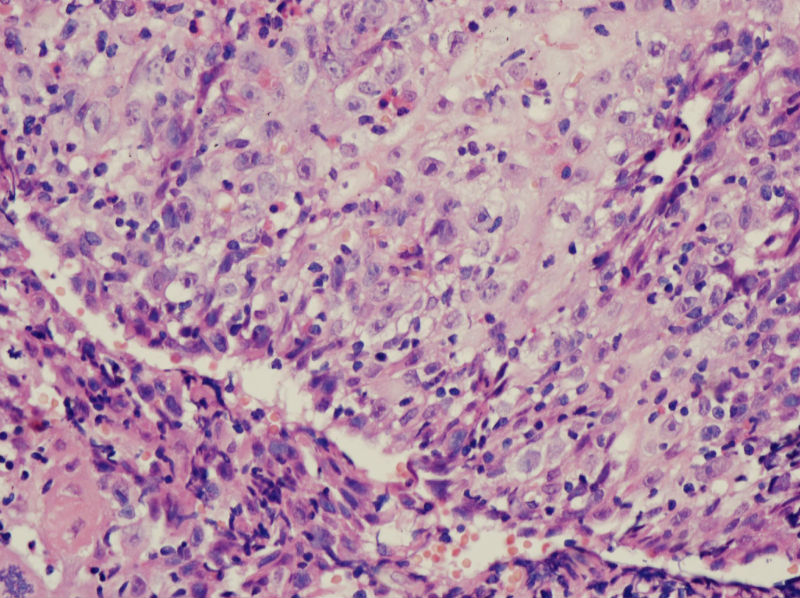

男,45岁,上唇菜花样肿物,请老师指教

图3